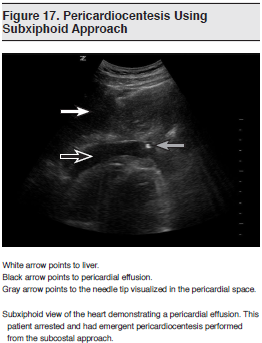

For years, clinicians have been instructed to carry out emergent pericardiocentesis using a blind subxiphoid approach, with a complication rate reported to be near 50%.152 Complications include ventricular puncture, coronary vascular laceration, pneumothorax, visceral abdominal puncture, and diaphragmatic injury. Bedside cardiac ultrasound guidance during this procedure has been shown by multiple authors to decrease the risk of these complications.153-157 (See Figure 17.) The largest of these studies examined a series of 1127 patients over a period of 21 years and noted a complication rate below 5%, well below the rate reported for standard pericardiocentesis using the landmark-based approach. The same group published a study of pericardiocentesis in pediatric patients in which the use of ultrasound guidance not only resulted in a lower complication rate but also reduced the need for repeat drainage and surgical intervention, probably owing to more accurate catheter placement and increased drainage made possible by direct ultrasound visualization.158 Interestingly, most authors note that the subxiphoid approach may not be the optimal approach, and that with ultrasound guidance, the parasternal or apical approach may provide more direct access to pericardial fluid.

One potential criticism of these studies is that they were carried out by cardiologists in a cardiology laboratory using large, cumbersome diagnostic echocardiography machines, which are not readily available in the ED. Despite this, the same basic principle of increased safety with direct visualization should apply in emergency situations. In addition, one group has looked at the utility of hand-carried ultrasound for procedural guidance during pericardiocentesis and thoracentesis. Although a small study, their results indicate that this is not only feasible but also increases patient safety.159